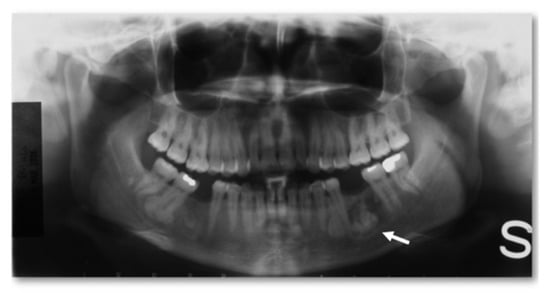

- Central, characterized by progressive endosseous development, eventually resulting in the complete replacement of the affected bone segment (Figure 1);